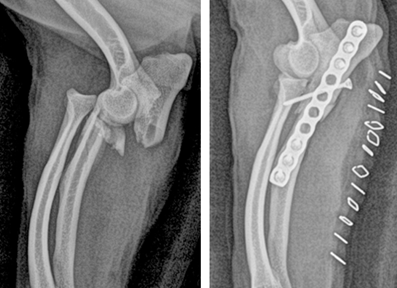

선천성 기형 및 사지 변형 (Angular Limb Deformities)

선천성 기형 및 사지 변형은 반려동물의 정상적인 사지 성장과 기능에 영향을 미치는 문제로, 본원에서는 3D CT 기반의 정밀한 분석을 통해 변형 부위를 정확히 진단하고, 교정 절골술을 시행하여 정상적인 골격 구조와 움직임 회복을 목표로 치료합니다.